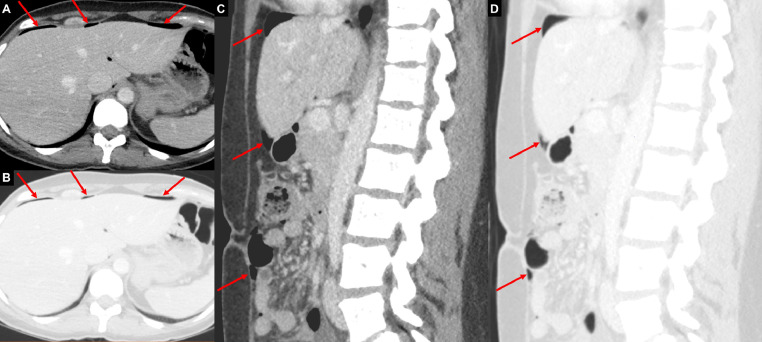

Fig. 2.

Case 2: Axial (A, B) and sagittal (C, D) CT images from the abdomen with soft tissue (A, C) and lung (B, D) windows demonstrate foci of free intraabdominal air (red arrows) at the anterior non-dependent abdomen.